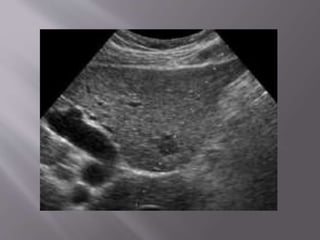

Liver biopsies are performed for both focal and

nonfocal lesions.

The primary indication for parenchymal liver

biopsy is for the diagnosis of hepatic disease.

When imaging guidance is employed, it can

take one of two forms:

US-guided "marking" in which a mark is made

upon the skin during US examination for a

biopsy to be performed later without imaging

guidance or real-time US guidance.

The patient is positioned supine, with the

hands comfortably resting behind the head

A preliminary US scan is performed to identify

the target and mark the skin.

The preliminary scan also ensures that no major

vessels, dilated biliary channels or gall bladder are

in the path of the biopsy needle.

Before the procedure is started, breathing

instructions are practiced with the patient.



performed with the breath held in expiration.

The skin site is prepped and draped to ensure

asepsis The local area is anesthetized with a

local anesthetic.

The cutting needle is then fired with US

documentation of the site.